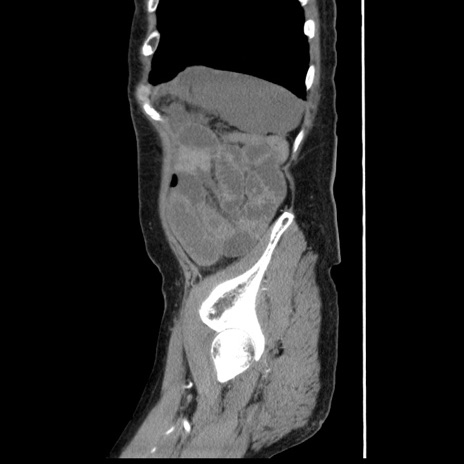

症例1(矢状断像)

【症例】80歳代女性

【主訴】腹痛

【現病歴】8時間前から腹痛あり来院。

【既往歴】糖尿病、脂質異常症、子宮体癌にて子宮全摘術

【身体所見】意識清明・会話良好だが腹痛で苦悶様、全腹部にわたって反跳痛と圧痛あり

【データ】WBC 13600、CRP 0.14、LDH 224、CK 90